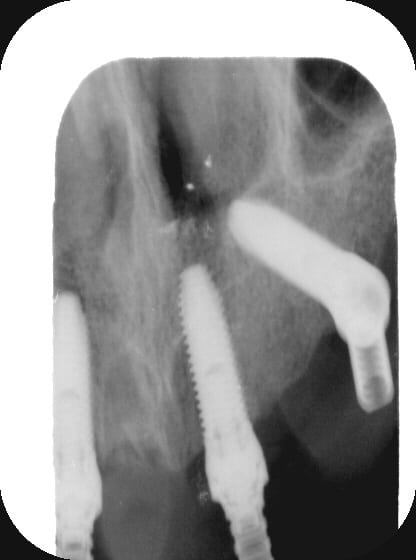

Tu as vraiment bien réussi à longer le plancher sinusal et apparemment la patiente pourra se pendre aux implants...

Tu as utilisé des Nobel Speedy si je ne me trompe pas.

Peux tu nous en dire un peu plus sur les implants, leurs diamétres et leur longueurs ?

du 4 par 15 ?